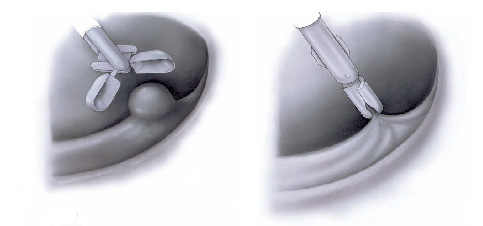

Polipectomia com alça diatérmica

Pólipos maiores necessitam ser removidos com alça e corrente de cauterização. Este procedimento permite cortar a base do pólipo e ao mesmo tempo coagular o local para evitar sangramentos.

Porém alguns pólipos possuem a base (pedículo) largo onde passam vasos calibrosos e por isto tem risco aumentado de sangramento na retirada mesmo usando a corrente de coagulação.

Nestes casos algumas medidas podem ser realizadas para diminuir o risco de sangramento:

Injeção de adrenalina na base do pólipo

Colocação de um laço na base do pólipo para estrangular o pedículo

Alguns pólipos são tão grandes que não podem ser removidos inteiros. Nestes casos o pólipo é retirado em pedaços para poder garantir a sua remoção completa.